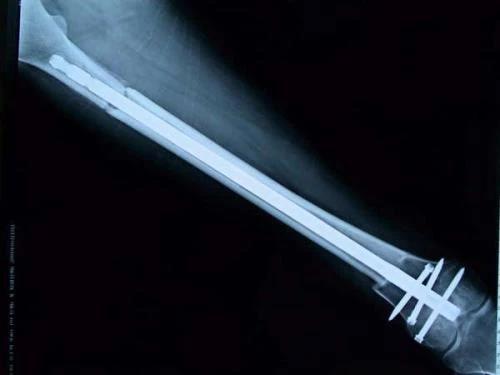

保肢治療指經(jīng)典型骨肉瘤在多學(xué)科團(tuán)隊醫(yī)生共同努力下完成的新輔助化療、保肢手術(shù)和輔助化療等一系列治療總稱,其目的是在提高患者生存率的前提下,減少局部復(fù)發(fā)、盡量保留良好的肢體功能。肢體經(jīng)典型骨肉瘤保肢治療方法如下圖所示: